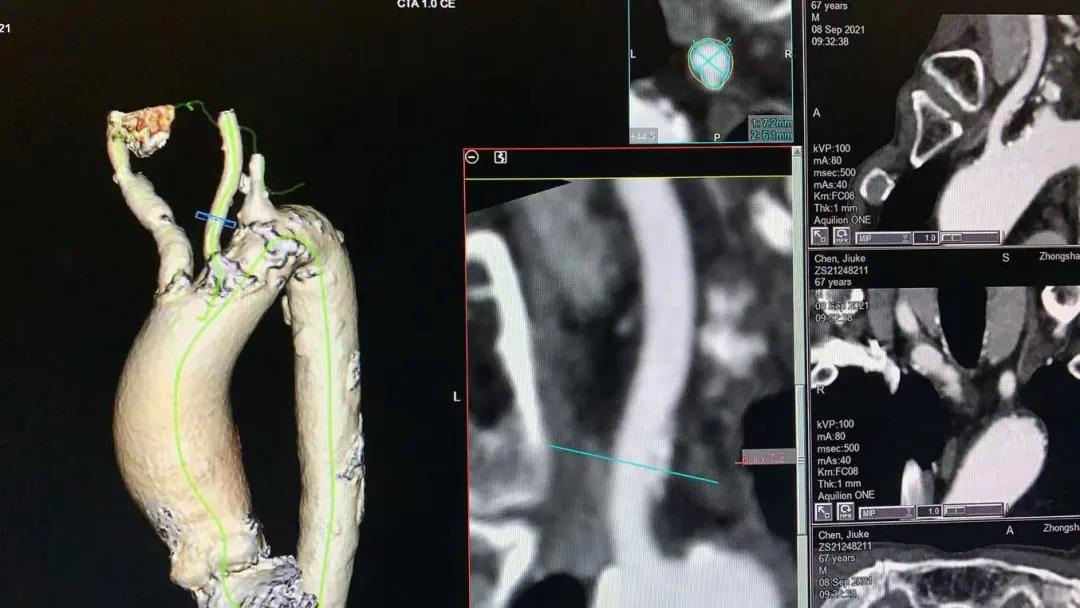

主动脉瓣瓣环 Type I型二叶瓣

瓣叶及左右冠瓣融合嵴重度钙化 重度肺气肿、多发肺大泡

患者男性,67岁,头晕伴胸闷、胸痛6月余,术前心脏超声提示主动脉瓣增厚钙化伴重度狭窄,峰值流速4.9m/s,峰值压差94mmHg,平均跨瓣压差59mmHg,瓣口面积0.6cm2。CT显示主动脉瓣为Type I型二叶瓣,瓣叶边缘及左右冠瓣融合嵴严重钙化,致瓣口极度细窄。瓣环面积528.8mm2,测算直径25.9mm,左冠脉开口高度14.4mm,右冠脉开口高度17.5mm。患者合并重度肺气肿、多发肺大泡、支气管扩张,肺功能极差,静息状态下氧饱和度仅约80%,STS评分8.6%,属于外科手术高风险患者。

CT重建显示患者双侧髂动脉、股动脉、锁骨下动脉质量极差,多发钙化狭窄伴局部夹层,无法经股动脉和锁骨下动脉入路。而且患者重度肺气肿致心脏两侧受压,心尖被压缩在胸骨及肋弓骨性融合后方,亦无法经心尖入路。评估双侧颈动脉近端均有钙化斑块伴轻度狭窄,平均管径约6mm,左侧管径略大于右侧。颅内Willis环交通支通畅,可以耐受经单侧颈动脉介入手术。